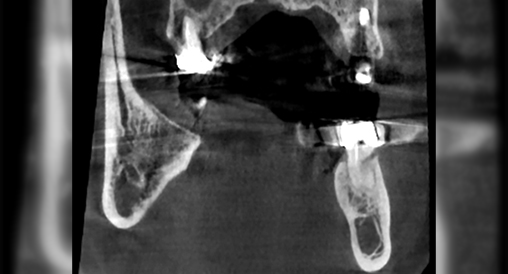

Технология уменьшения артефактов ART-V

Металлические предметы ухудшают визуализацию и снижают точность диагностики. Алгоритм для уменьшения влияния металлических артефактов снижает отражение рентгеновских лучей от плотных объектов, что повышает качество диагностики.

ART-V Off

ART-V On